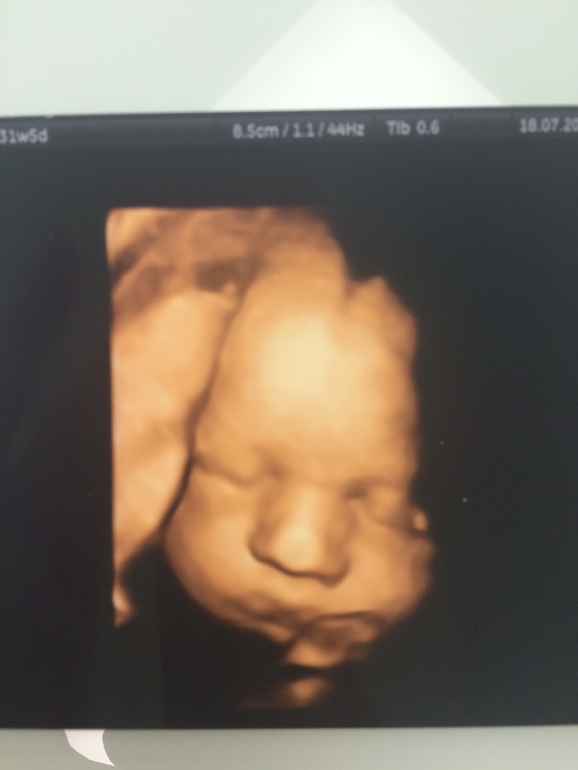

Наконец-то я выдохнула с облегчением - наш малыш хорошо развивается по всем показателям и весит уже 1800 г!:) Была я у доктора Батаевой в Центре Медицины Плода - как всегда довольна. Однако, есть одно НО - плацента у меня поднялась, но не до положенного уровня - 5,5 см (надо 7 см). Доктор сказала, что в Европе рожают сами с такой плацентацией, но в России она бы рекомендовала КС. Я вот теперь в раздумьях... Шейка еще 5,5 см - я похоже так боялась преждевременных, что отрастила шейку невероятной длины)))) У кого-то была подобная ситуация с плацентой? Как вы рожали?

P.S. А вот наш сыночек =^_^=

Какое классное фото! Только вот интересовалась 3д узи и у вас вижу, что круто!💐